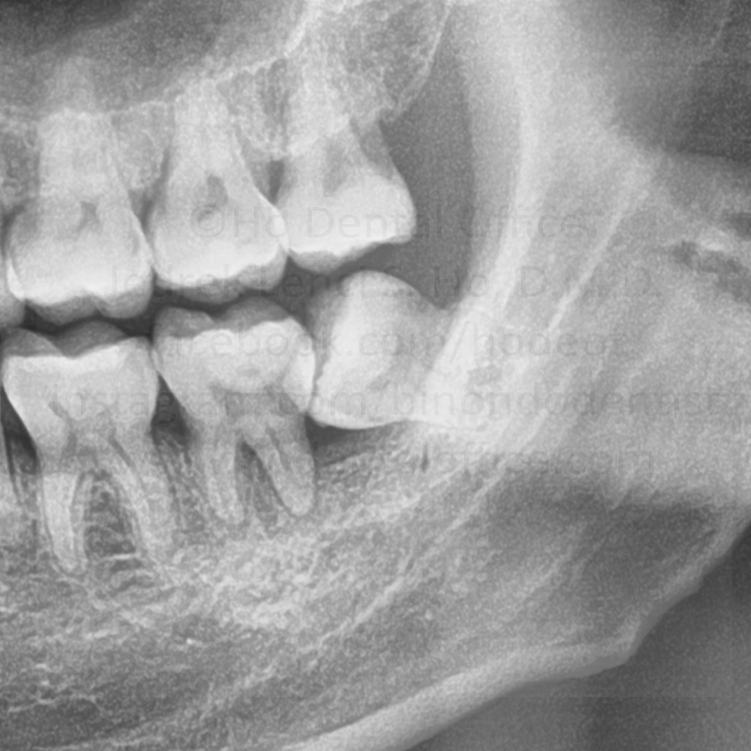

prevention of tooth decay - Food impaction is relatively common on exposed partially impacted tooth, and may damage the neighboring tooth because of cleaning difficulties.

![]() | ![]() |

| tooth decay on the lower second molar, beside the impacted wisdom tooth | |